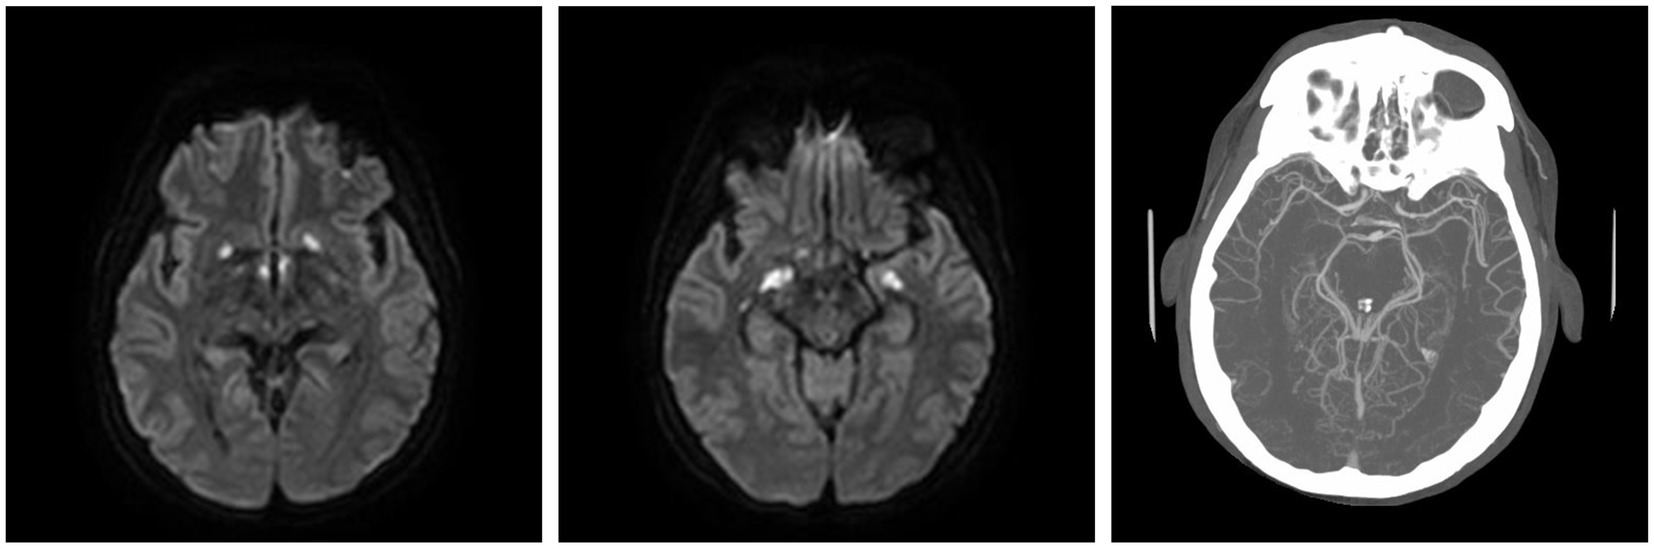

Case report: We present a case of a 43-year-old man who was diagnosed with THS 10 weeks prior to his final hospital presentation. Previous infectious work up was negative. He returned with altered mental status and was found to have leptomeningeal enhancement, vasculitis, and acute infarcts. He decompensated while on broad-spectrum antimicrobials. The patient was ultimately found to have CNS actinomycosis when next generation sequencing identified Actinomyces israelii. This diagnosis was confirmed by biopsy. Unfortunately, due to the extent of the infarcts, the patient passed away.

Furthermore, 6 weeks after his initial presentation, follow-up MRI revealed an increase in the size of the cavernous sinus lesion from 1.7 × 1.7 × 1.6 cm to 1.8 × 2.0 × 1.8 cm, demonstrating further extension of the lesion into the Meckel’s cave and along the trigeminal maxillary division, accompanied by further narrowing of the left ICA (Figure 1). He underwent a positron emission tomography (PET) scan to evaluate for other areas of malignancy/granulomatous disease, with the differential diagnoses being unchanged. The patient continued to experience headaches; however, cranial nerve III and VI palsies and diplopia had resolved.

Moreover, 13 weeks after the initial presentation, he returned to the ED with altered mental status and was admitted for evaluation. On examination, he demonstrated word-finding difficulties, impaired attention, and neck stiffness. No other focal signs were noted. MRI re-imaging demonstrated new leptomeningeal enhancement and acute strokes of the bilateral basal ganglia, hypothalamus, and medial temporal lobes, with vascular imaging demonstrating multifocal stenoses with bilateral ICA involvement (Figure 2). The CSF studies revealed significant neutrophilic pleocytosis with an elevated white blood cell count (WBC) of 3,089 uL (72% polymorphonuclear neutrophils (PMNs)), hypoglycorrhachia (35 mg/dL), and elevated protein (124 mg/dL; Table 1). Infectious workup, including bacterial, fungal, and acid-fast cultures; BioFire Meningitis/Encephalitis PCR panel; Nocardia cultures; cryptococcal antigen; and Toxoplasma PCR, was negative. Broad-spectrum antimicrobials, including vancomycin, ceftriaxone, ampicillin, acyclovir, and amphotericin, were initiated for empiric meningitis coverage, covering typical and atypical bacterial, viral, and fungal meningitides in the setting of a seemingly indolent course. Ampicillin and acyclovir were quickly discontinued due to negative testing. The patient was tapered off outpatient steroids during hospitalization. Despite serial CSF studies showing an improving cell count (Table 1), symptoms continued to worsen, leading to a comatose state, which resulted in the patient being intubated and transferred to the intensive care unit on hospital day 3. Serial imaging showed new and expanding regions of diffusion restriction involving the basilar artery territory, as well as proximal posterior cerebral artery stenosis presumably secondary to vasospasm (Figure 3). Magnetic resonance angiography of the head showed enhancement around the basilar artery, raising concern for infectious vasculitis.

Given the patient’s worsening clinical symptoms and negative microbiologic workup, a serologic NGS test (Karius Test) was performed, which returned positive for Actinomyces israelii at 61 DNA molecules per microliter (MPM) and human herpesvirus 7 (HHV7) at 30 DNA MPM. The pathogenicity of Actinomyces was undetermined, while HHV7 was thought to be incidental. To confirm clinical significance, a transsphenoidal skull base incision and drainage were performed, revealing a necrotic-appearing pituitary gland and readily expressed purulent fluid. Pathological examination showed sulfur granule-like aggregates of branching filamentous bacteria consistent with Actinomyces (Figure 4). Targeted tissue NGS (Broad-Range PCR) also revealed trace Actinomyces israelii, further confirming the diagnosis of CNS actinomycosis. Broad-spectrum antibiotics were narrowed to IV ceftriaxone. Antibiotics were not further narrowed due to the presence of Gram-indeterminate cocci, which were suspected to represent either a secondary bacterial infection or dysmorphic actinomyces. Given the extensive infarcts involving the basal ganglia, thalami, brainstem, and cortices, the family elected to pursue comfort measures. The patient expired shortly after compassionate extubation, approximately 9 days after the suspected diagnosis of CNS actinomycosis. The autopsy revealed diffuse edema and purulence at the skull base, with areas of necrosis and inflammation extending to the walls of the large-caliber vessels. There were regions showing signs of subacute infarcts and meningitis as well. The cause of death was determined to be brain abscess formation with subsequent acute and chronic meningitis (Figure 5). A timeline of the patient’s disease course is provided in Figure 6.